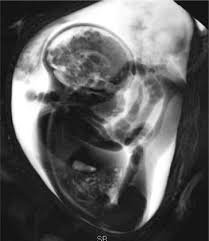

La posición podálica fetal se refiere a cuando el bebé se encuentra sentado dentro del útero, es decir, con las nalgas o los pies orientados hacia el canal de parto en lugar de la cabeza. Esta presentación puede implicar desafíos durante el parto, por lo que su detección temprana es fundamental para garantizar la seguridad de la madre y el bebé.

Mediante una sonografía obstétrica, es posible identificar esta posición con precisión, lo que permite al equipo médico planificar el tipo de parto más adecuado y seguro. En NatalMedica, acompañamos cada etapa del embarazo con un enfoque integral, brindando atención especializada, tecnología de vanguardia y el compromiso de cuidar lo más importante: tu bienestar y el de tu bebé.